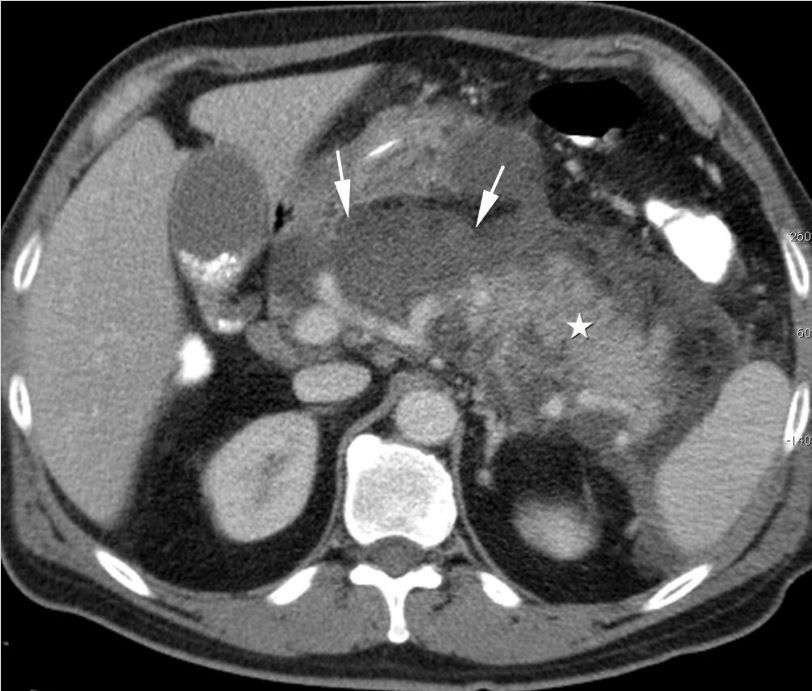

The typical features of acute pancreatitis on CT scan are as follows: - focal / diffuse enlargement of parenchyma - altered density secondary to edema - indistinct margins of pancreas secondary to swelling - retroperitoneal fat stranding Reference: https://radiopaedia.org/articles/acute-pancreatitis Image via: https://www.pancreapedia.org/reviews/imaging-assessment-of-etiology-and-severity-of-acute-pancreatitis